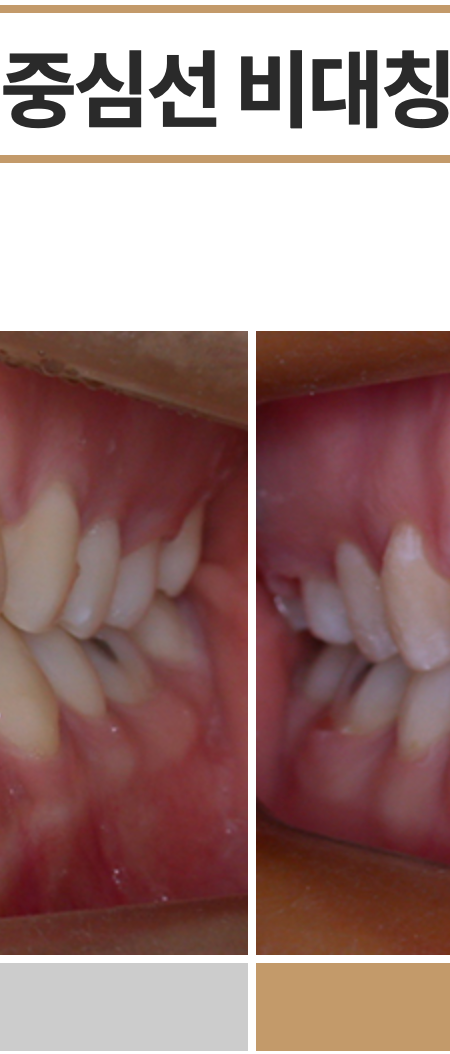

위 사진을 보시면 왼쪽 사진은

작은 어금니를 발치한 후 촬영한 모습이고,

오른쪽 사진은 소구치를 발치한

빈 공간으로 앞니를 어느 정도 이동시켜

치열을 다시 재배열중인 모습입니다.

작은 어금니보다 안쪽에 위치한

큰 어금니들을 기준으로 앞니가

뒤쪽으로 이동한 모습인데요.

그래서 전과 비교하여도

교합이나 어금니의 위치에

큰 변화가 생기지 않았다는 것을

확인하실 수 있으실겁니다.